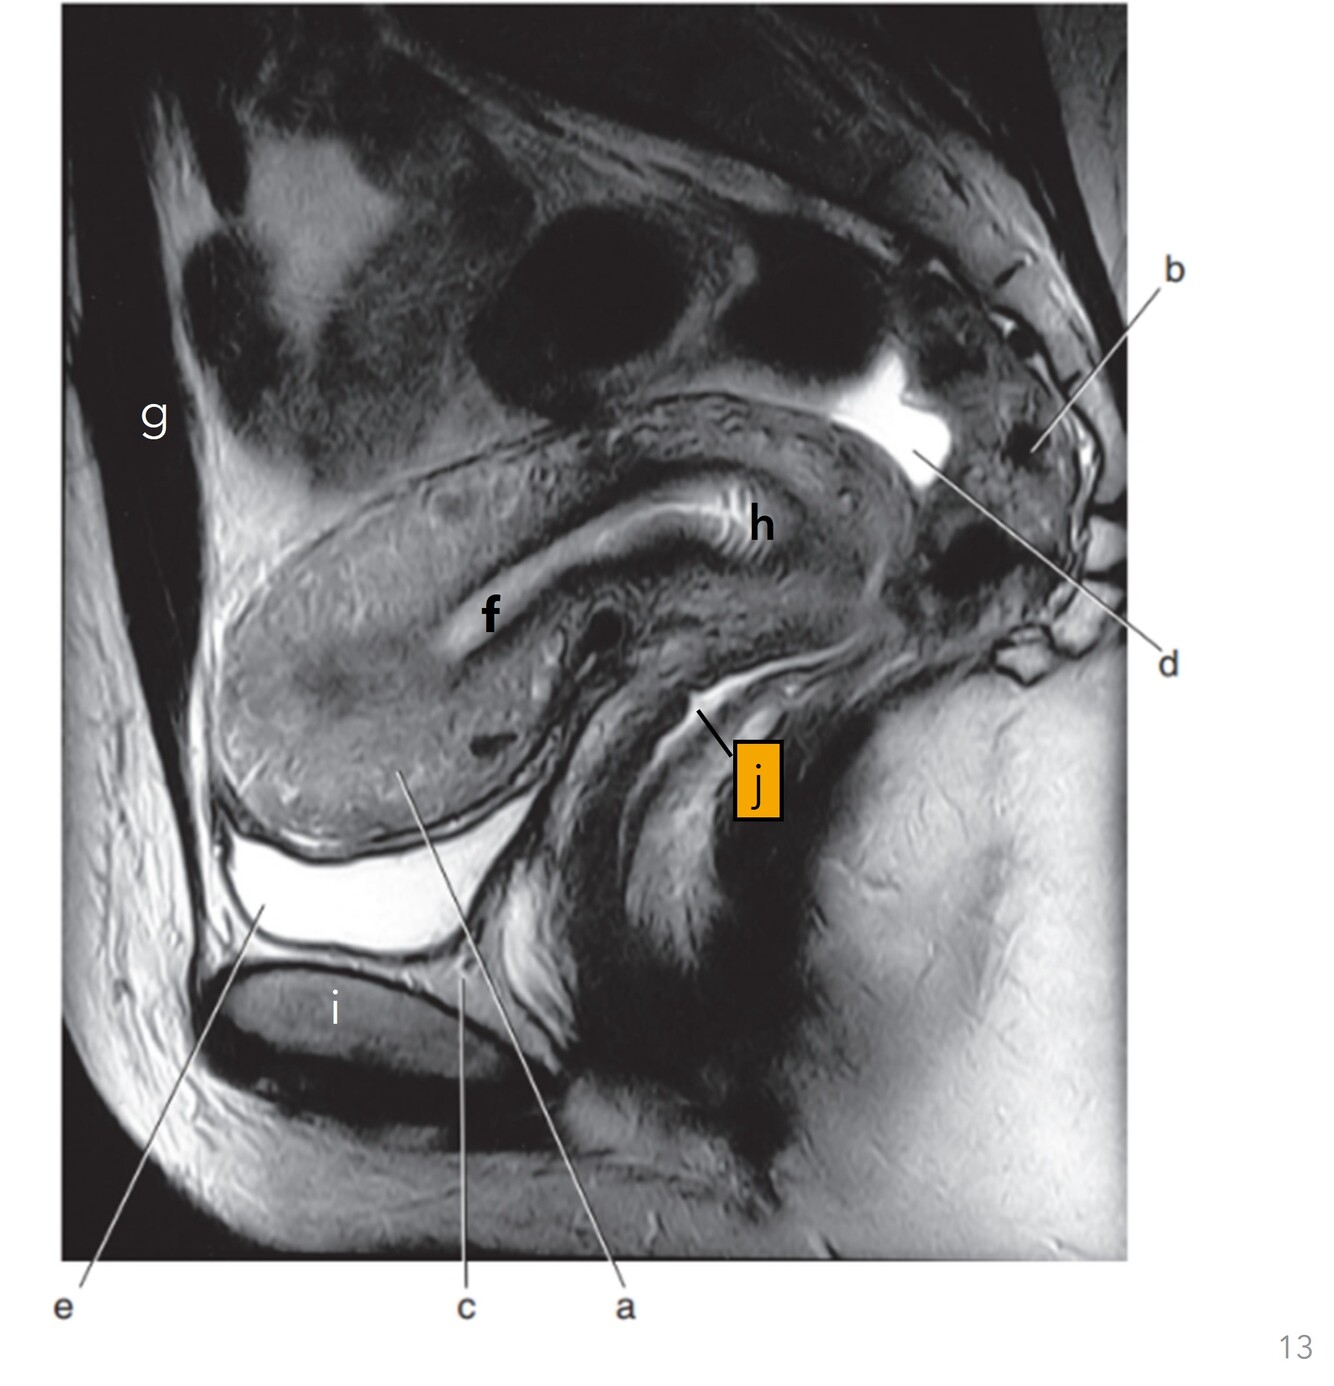

13

Q

Label a-e

A

a. Myometrium (uterus)

b. Rectum

c. Retropubic space

d. Pouch of Douglas/Rectouterine space

e. Bladder

How well did you know this?

14

Label f-j

f-Uterine cavity

g-Rectus abdominis

h-Cervix

i-Pubis symphysis

j-Vagina